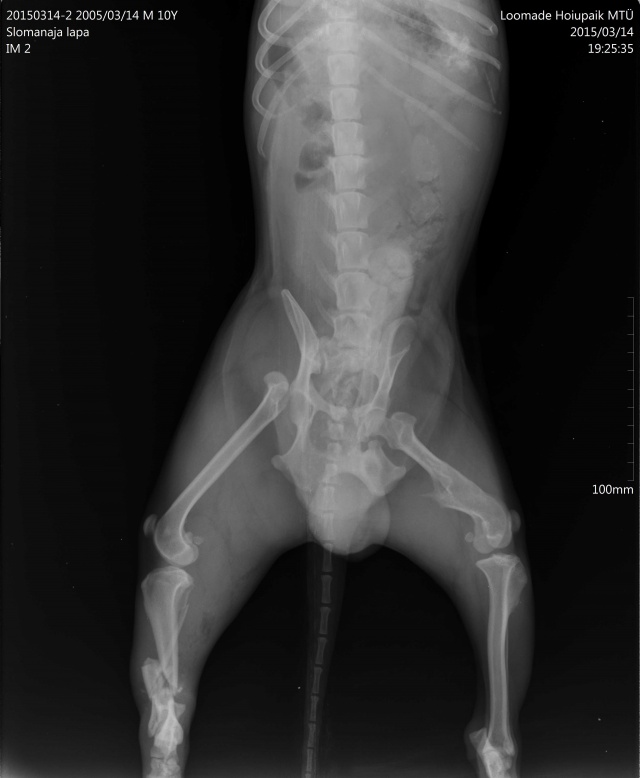

Tagumise käpa luumurd.

Koerake sattus varjupaika vigastatud käpaga. Ülevaatusel selgus, et koera käpal on mitmekordne luumurd. Pidime paigaldama ka kateetri, kuna ta ei saanud pissida (ilmselt autolöögist põhjustatud kusepõie atoonia).

Собака поступила в приют с множественным переломом ноги. Не могла пописать (видимо был удар машины и, как результат, атония мочевого пузыря). Нога в очень тяжёлом состоянии, и завтра мы кладём собаку на операционный стол.